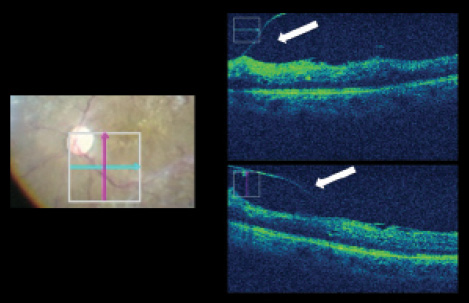

Figure 1. Patient with ERM and persistent vitreous attachments with vitreoschisis (arrows).

Detection of Architectural Changes During ERM Peeling

With intraoperative OCT, it was possible to detect and monitor retinal architectural changes that can occur during ERM peeling. Following posterior vitreous detachment (PVD), the Rescan 700 was a valuable surgical tool for intraoperative visualization of vitreoschisis (Figure 1). Despite surgical confirmation of PVD with no residual vitreous using intravitreal triamcinolone, intraoperative OCT offered immediate visualization of persistent vitreous layers and retinal anatomy before ERM peeling. In ERM and internal limiting membrane peeling, intraoperative OCT technology contributed significantly to the understanding of intraoperative traumatic changes caused by the peeling procedure, and the ability to assess intraretinal thickness and intraretinal cysts intraoperatively was very useful.